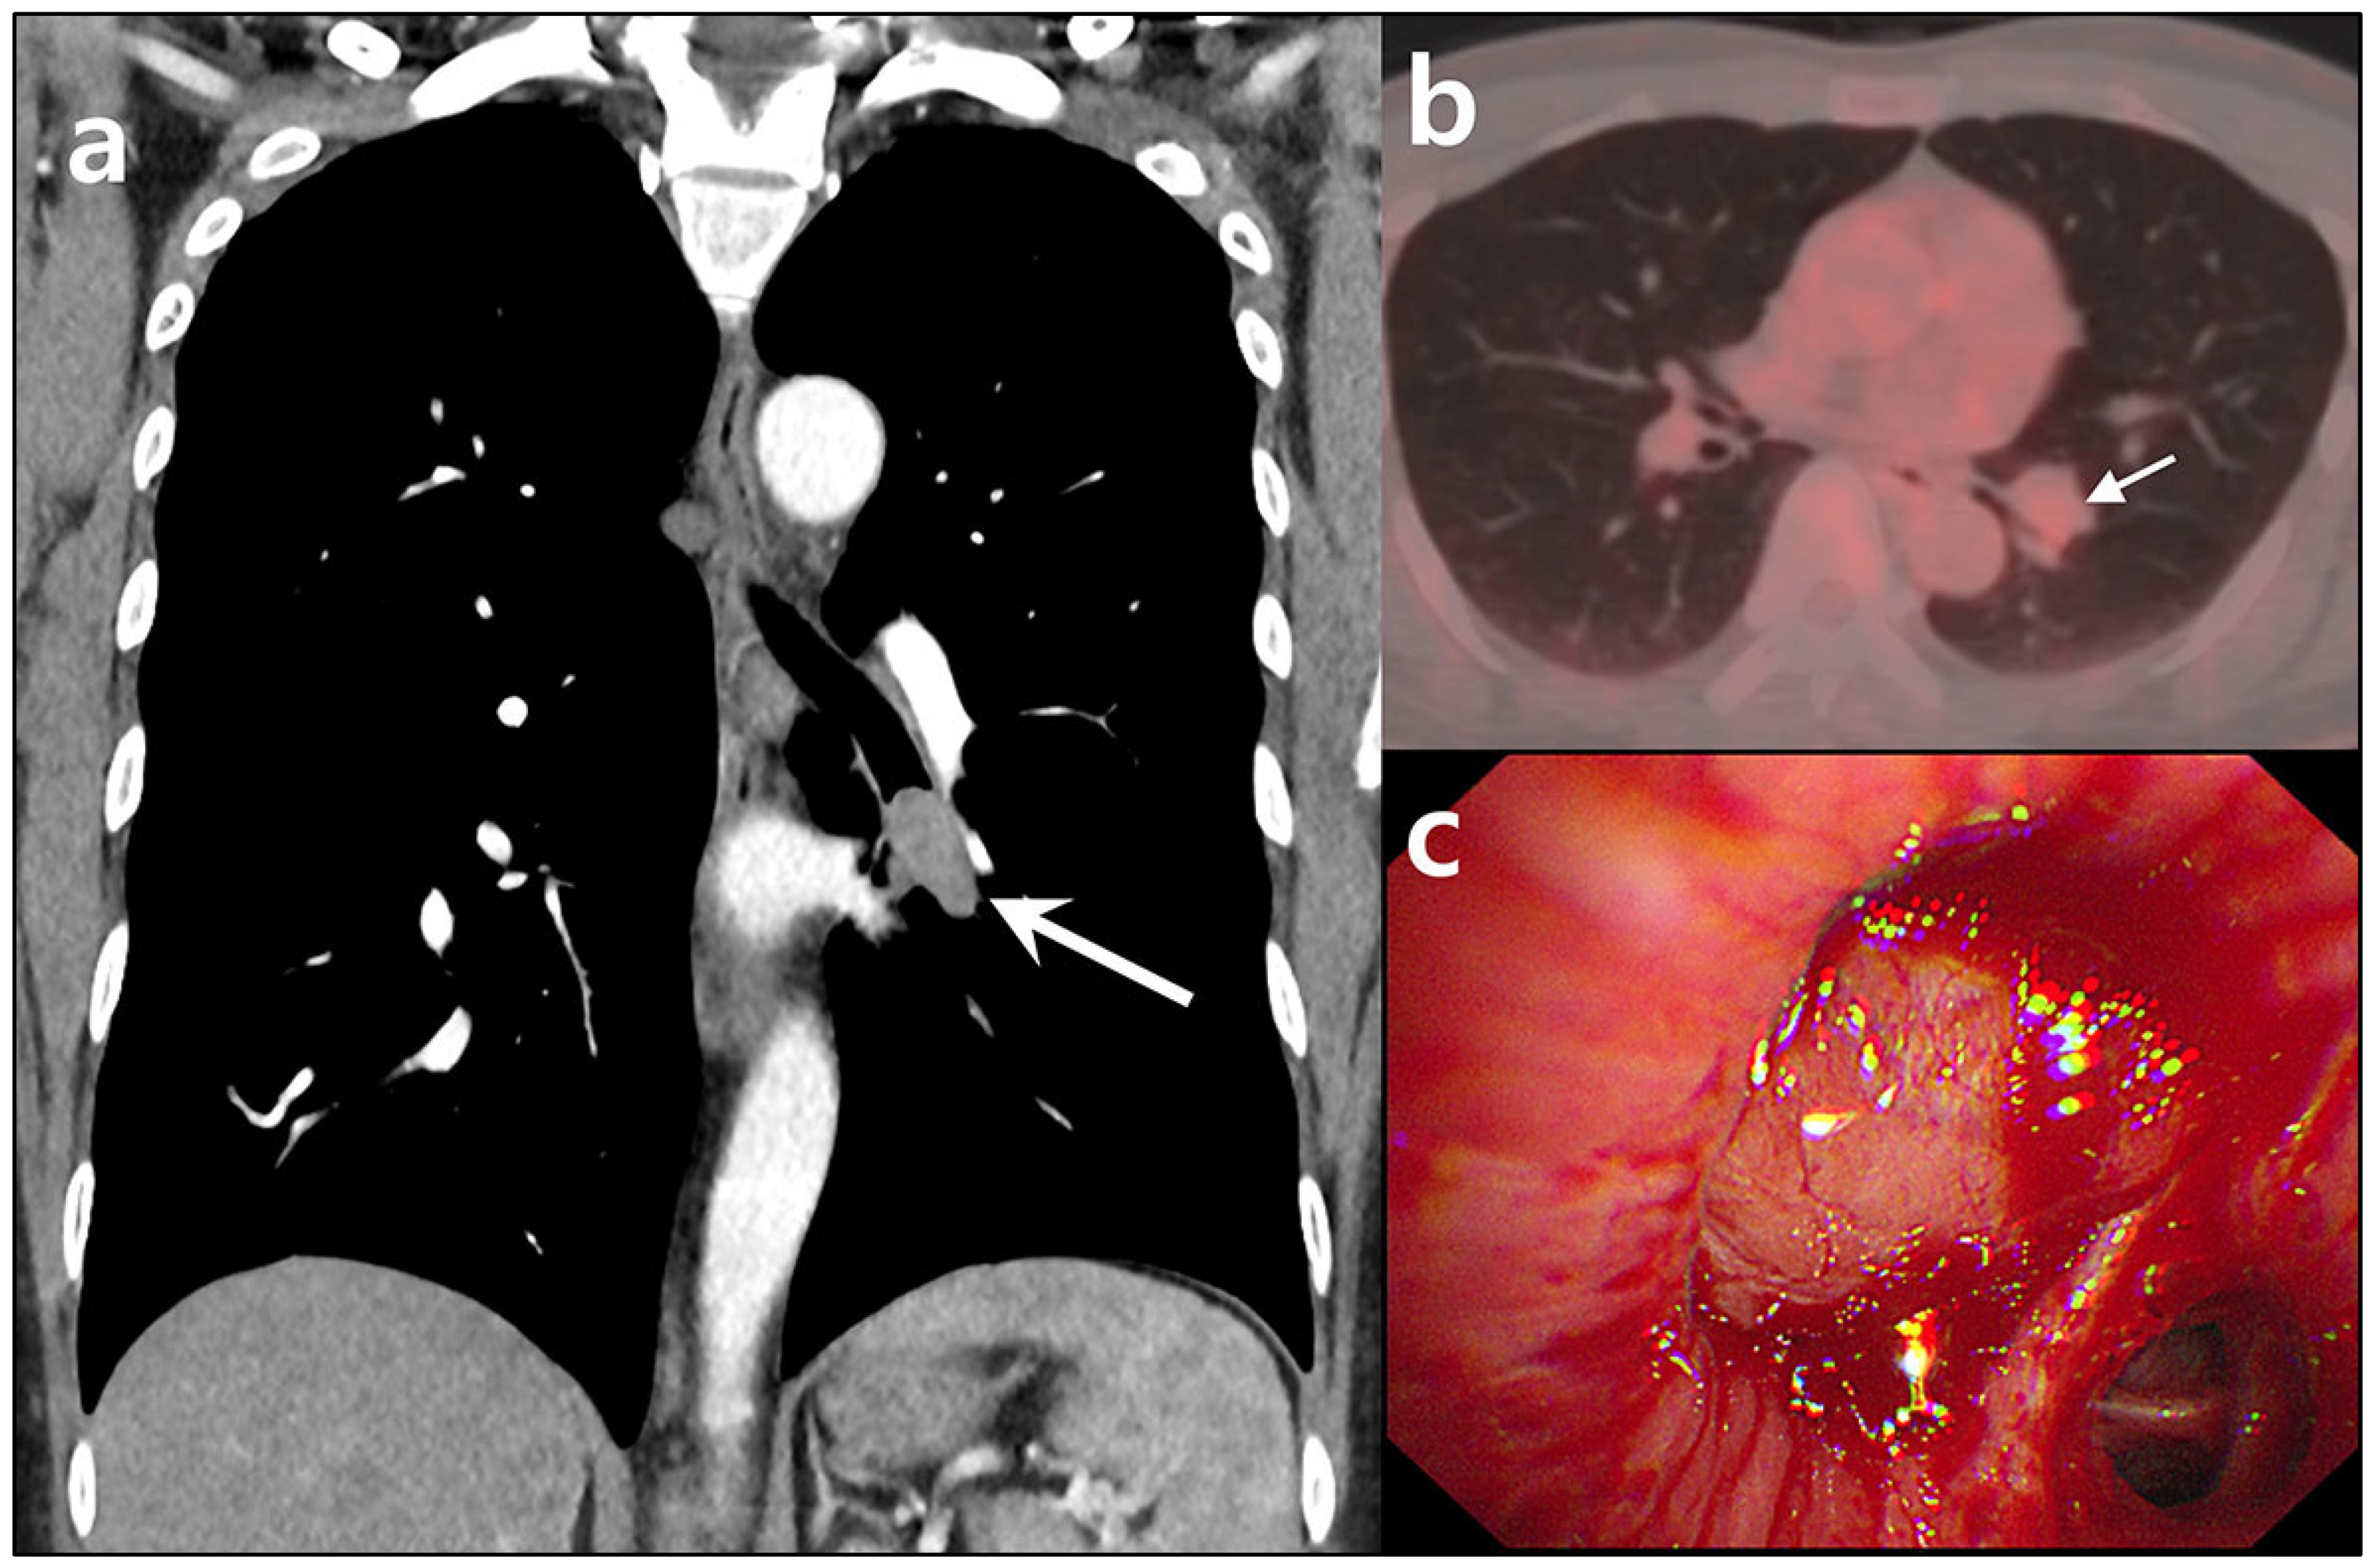

Central Airway Carcinoid Tumorlets Following Resection of a Typical Carcinoid Tumor

Bae, K.; Jeon, K.N.; Heo, I.R.; An, H.J.; Song, D.H. Central Airway Carcinoid Tumorlets Following Resection of a Typical Carcinoid Tumor. Diagnostics 2025, 15, 1651. https://doi.org/10.3390/diagnostics15131651